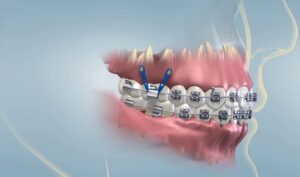

Bác sĩ Chuyên khoa I Cang Hồng Thái hiện là Giám đốc Nha Khoa Đông A và có hơn 20 năm kinh nghiệm trong lĩnh vực cấy ghép Implant, chỉnh nha, phục hình răng thẩm mỹ. Ông đã làm việc tại các bệnh viện lớn như Răng Hàm Mặt và Đại học Y Dược TPHCM.

Bác sĩ Thái cũng là thành viên của Hiệp hội Nha khoa Hoa Kỳ AAO và Liên đoàn Chỉnh nha Thế giới WFO. Ông được biết đến là chuyên gia hàng đầu, chuyên tiếp nhận và xử lý các trường hợp khó hoặc bị từ chối ở các cơ sở Nha khoa khác.

Mỗi năm, có hơn 4000 khách hàng từ trong và ngoài nước đến điều trị thành công với bác sĩ Thái. Trong quá trình tư vấn và điều trị, ông luôn lắng nghe nhu cầu của bệnh nhân, giúp họ thoải mái và hiệu quả nhất. Mọi kế hoạch điều trị của ông đều dựa trên nghiên cứu kỹ lưỡng, nhằm bảo tồn răng gốc tối đa.